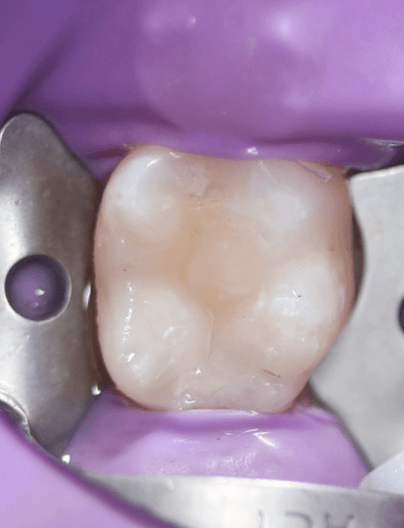

Polishing

I go with cusp by cusp build up to recreate occlusal morphology. Followed by rugby ball and white stone polishing.

The Final Result

Apologies for my out of focus photography! It was one of my first times using my new camera.